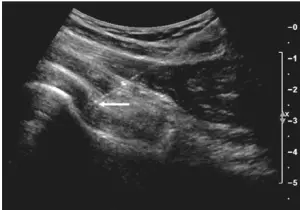

Dr. Domb and his team are highly trained in ultrasound-guided injections. These procedures are performed in the office at the time of your visit. The ultrasound machine assists the providers to safely place injectable medications into or around the joint.